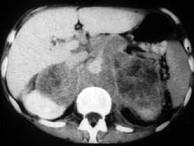

问题 男,76岁,全身浅表淋巴结肿大,请结合下列图片作出诊断()

选项 A.肾上腺腺瘤 B.肾上腺癌 C.肾上腺嗜铬细胞瘤 D.肾上腺转移瘤 E.肾上腺淋巴瘤

答案 E